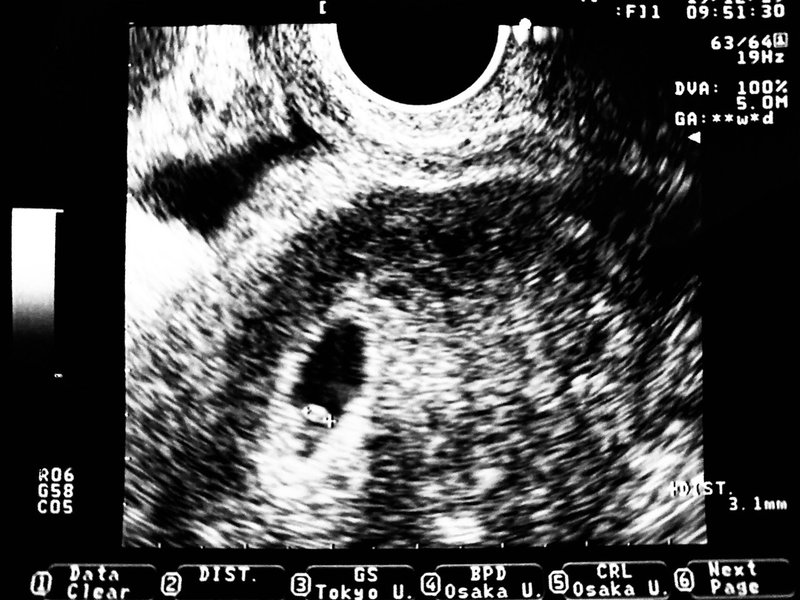

妊娠6週6日 6w6d の超音波 エコー 写真

妊娠6週4日 6w4d の超音波 エコー 写真

妊娠5週5日 5w5d の超音波 エコー 写真

産婦人科医監修 胎嚢 たいのう の大きさの平均は 妊娠4週 5週 6週 7週 8週の目安は 週数別に解説 ままのて